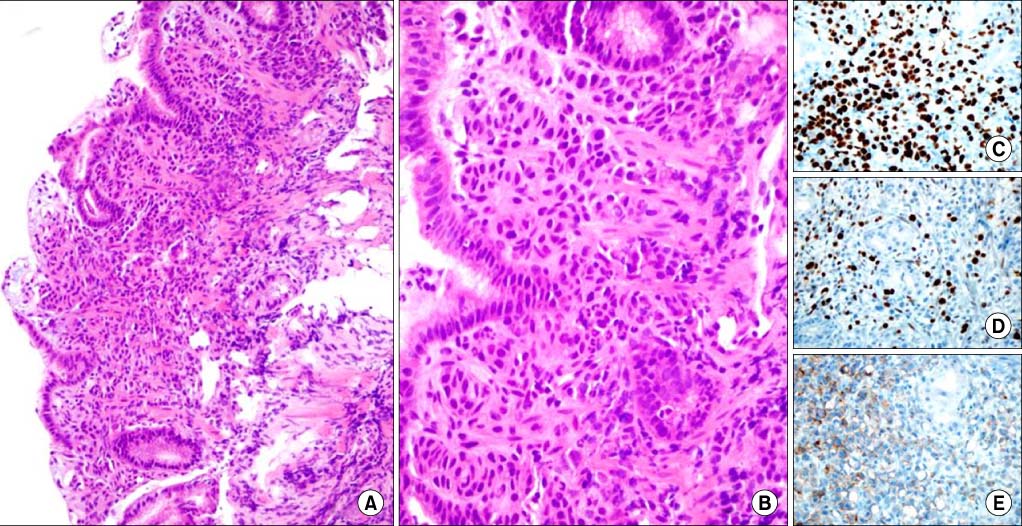

Microscopic findings. They show that the tumor cells of Invasive lobular carcinoma of breast arepositive for estrogen receptor (ER) and progesteron receptor (PR), Her2/neu. (A) Invasive lobular carcinoma of breast (H&E, ×100). (B) Invasive lobular carcinoma of breast (H&E, ×400). (C) Positive immunohistochemistry for ER (×400). (D) Positive immunohistochemistry for PR (×400). (E) Weakly positive immunohistochemistry for Her2/neu (×400).

Fig. 1 Microscopic findings. They show that the tumor cells of Invasive lobular carcinoma of breast arepositive for estrogen receptor (ER) and progesteron receptor (PR), Her2/neu. (A) Invasive lobular carcinoma of breast (H&E, ×100). (B) Invasive lobular carcinoma of breast (H&E, ×400). (C) Positive immunohistochemistry for ER (×400). (D) Positive immunohistochemistry for PR (×400). (E) Weakly positive immunohistochemistry for Her2/neu (×400).